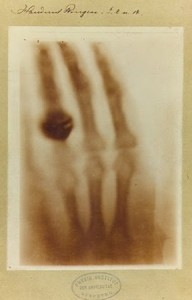

Fue el 8 de noviembre de 1895 cuando en el curso de sus investigaciones Roentgen, experimentando el poder de penetración de los rayos catódicos, observó que una placa de cartón cubierta de cristales, emitía una fluorescencia. Ésta desaparecía cuando desconectaba la corriente. Siguió repitiendo el experimento porque era partidario de la investigación y pronto descubrió que esos rayos (que él llamó «X») atravesaban distintos tipos de materiales pero no el plomo. También se dio cuenta de que al sostener un aro de plomo con sus dedos, no sólo veía el aro sino también los huesos de su mano. Se le ocurrió que podía «imprimir» la imagen en una placa fotográfica y fue así como hizo la primera radiografía. La mano que aparece en esta primera imagen es la de su mujer Bertha, quien siempre lo acompañó a lo largo de su vida. Más allá del cómo fueron descubiertos, es importante resaltar que para el investigador y para el creador en general, estar atento al curso de lo que va realizando es central, así como también lo es estar abierto y dispuesto a cambiar sobre la marcha de su creación. Si se busca una sola cosa, se pierden en el medio otras innumerables posibilidades.